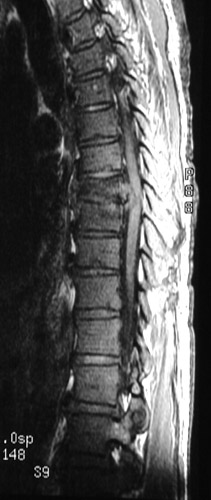

There is bony destruction of T8 and 9, consistent with osteomyelitis in this MRI scan in sagittal view. This is a case of tuberculous osteomyelitis (Pott's disease).